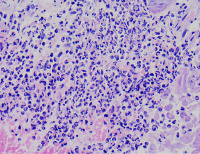

外阴多发赘生物,请教老师们,怎么报告?

性别

女

年龄

62

临床诊断

一般病史

发现外阴数十粒丘疹样结节,伴溃疡

标本名称

外阴丘疹样赘生物

大体所见

灰白色组织两粒0.5*0.3cm

考虑:疱疹病毒感染

疱疹性皮炎。

符合疱疹性皮炎。